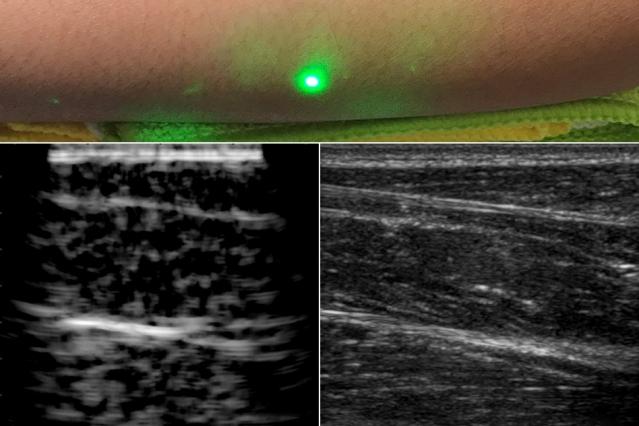

Dans le détail, le laser d'émission envoie une impulsion lumineuse qui est rapidement absorbée par la peau et convertie en ondes sonores par l'effet photo-acoustique, c’est-à-dire la génération de son par la lumière. Les ondes sonores générées interagissent avec des tissus identiques aux ultrasons conventionnels et les signaux réfléchis sont détectés par un interféromètre laser à la surface de la peau. Les lasers sont ensuite déplacés sur la surface de la peau pour produire une image.

Testé avec succès sur des sujets humains, ce système a montré que les ultrasons laser sont sensibles aux mêmes caractéristiques des tissus que ceux détectés par les ultrasons conventionnels. Il permet par ailleurs d'obtenir des images à des profondeurs de l'ordre du centimètre, ce qui est beaucoup plus profond que les autres techniques d'ultrasons optiques et est comparable aux profondeurs d'imagerie des ultrasons cliniques modernes.